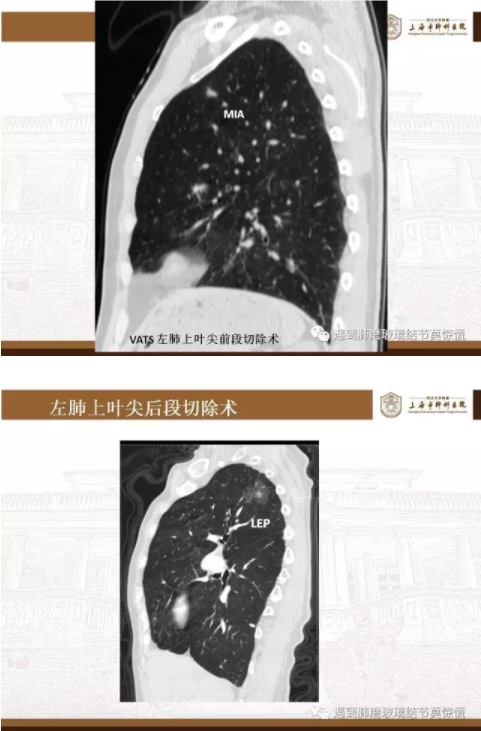

下面就我们的病例分析一下怎么进行肺段切除。

MIA= 微浸润腺癌   IA= 浸润性腺癌   AIS= 原位腺癌   AAH= 不典型腺瘤样增生